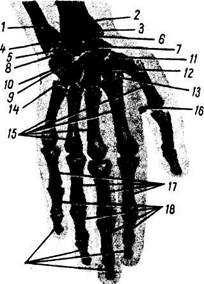

Рис. 50. Рентгенограмма кисти мужчины 38 лет; ладонная проекция.

/-локтевая кость; 2 — лучевая кость; 3 - шиловидный отросток лучевой кости; 4 - дистальный луче-локтевой сустав; 5 — треугольный хрящ; б — щель лучезапястного сустава; 7 — ладьевидная кость; S — полулунная кость; 9 — трехгранная кость; /0 — гороховидная кость; 11 — кость-трапеция; 12 — трапециевидная кость; 13 - головчатая кость; 14 - крючковидная кость; 15 — пястные кости; 16 — сесамовидная кость; 17 — проксимальные фаланги; 18 — средние фаланги; 19 — дистальные фаланги.

На ладонном рентгеновском снимке кисти видны все участвующие в ее образовании кости и их детали (рис. 50). «Рентгеновские суставные щели» имеют вид полос просветлений между суставными поверхностями соответствующих костей.

«Рентгеновская щель» лучезапястного сустава в медиальной части расширена соответственно расположенному здесь суставному диску (треугольному хрящу), не задерживающему рентгеновских лучей.